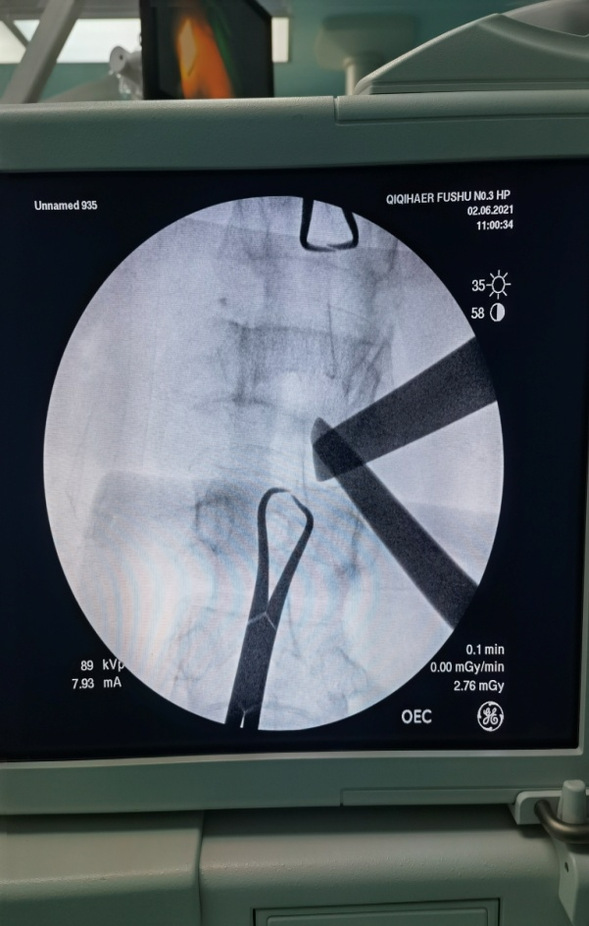

术中手术器械到达目标,建立手术空间